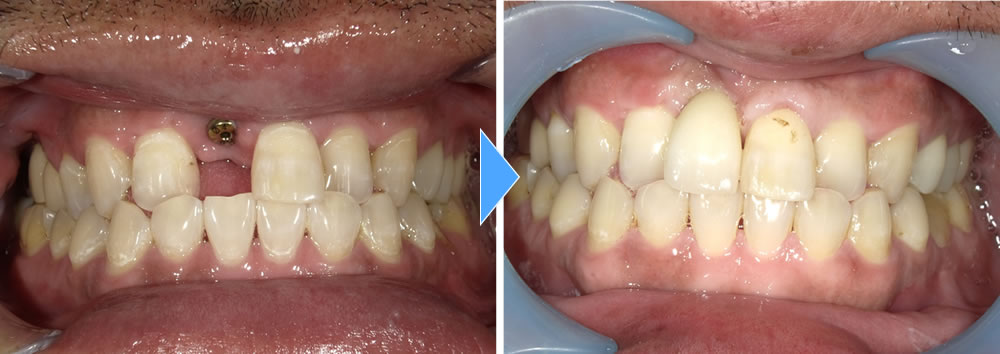

上部構造の装着・治療完了

術後は固いものを噛むことはもちろん、天然歯との違いがほとんどわからないほど自然な見た目になり、機能的にも審美的にも大変満足していただけました。

現在は定期的なクリーニングとホワイトニングにて通院していただき、キレイな状態を保っています。